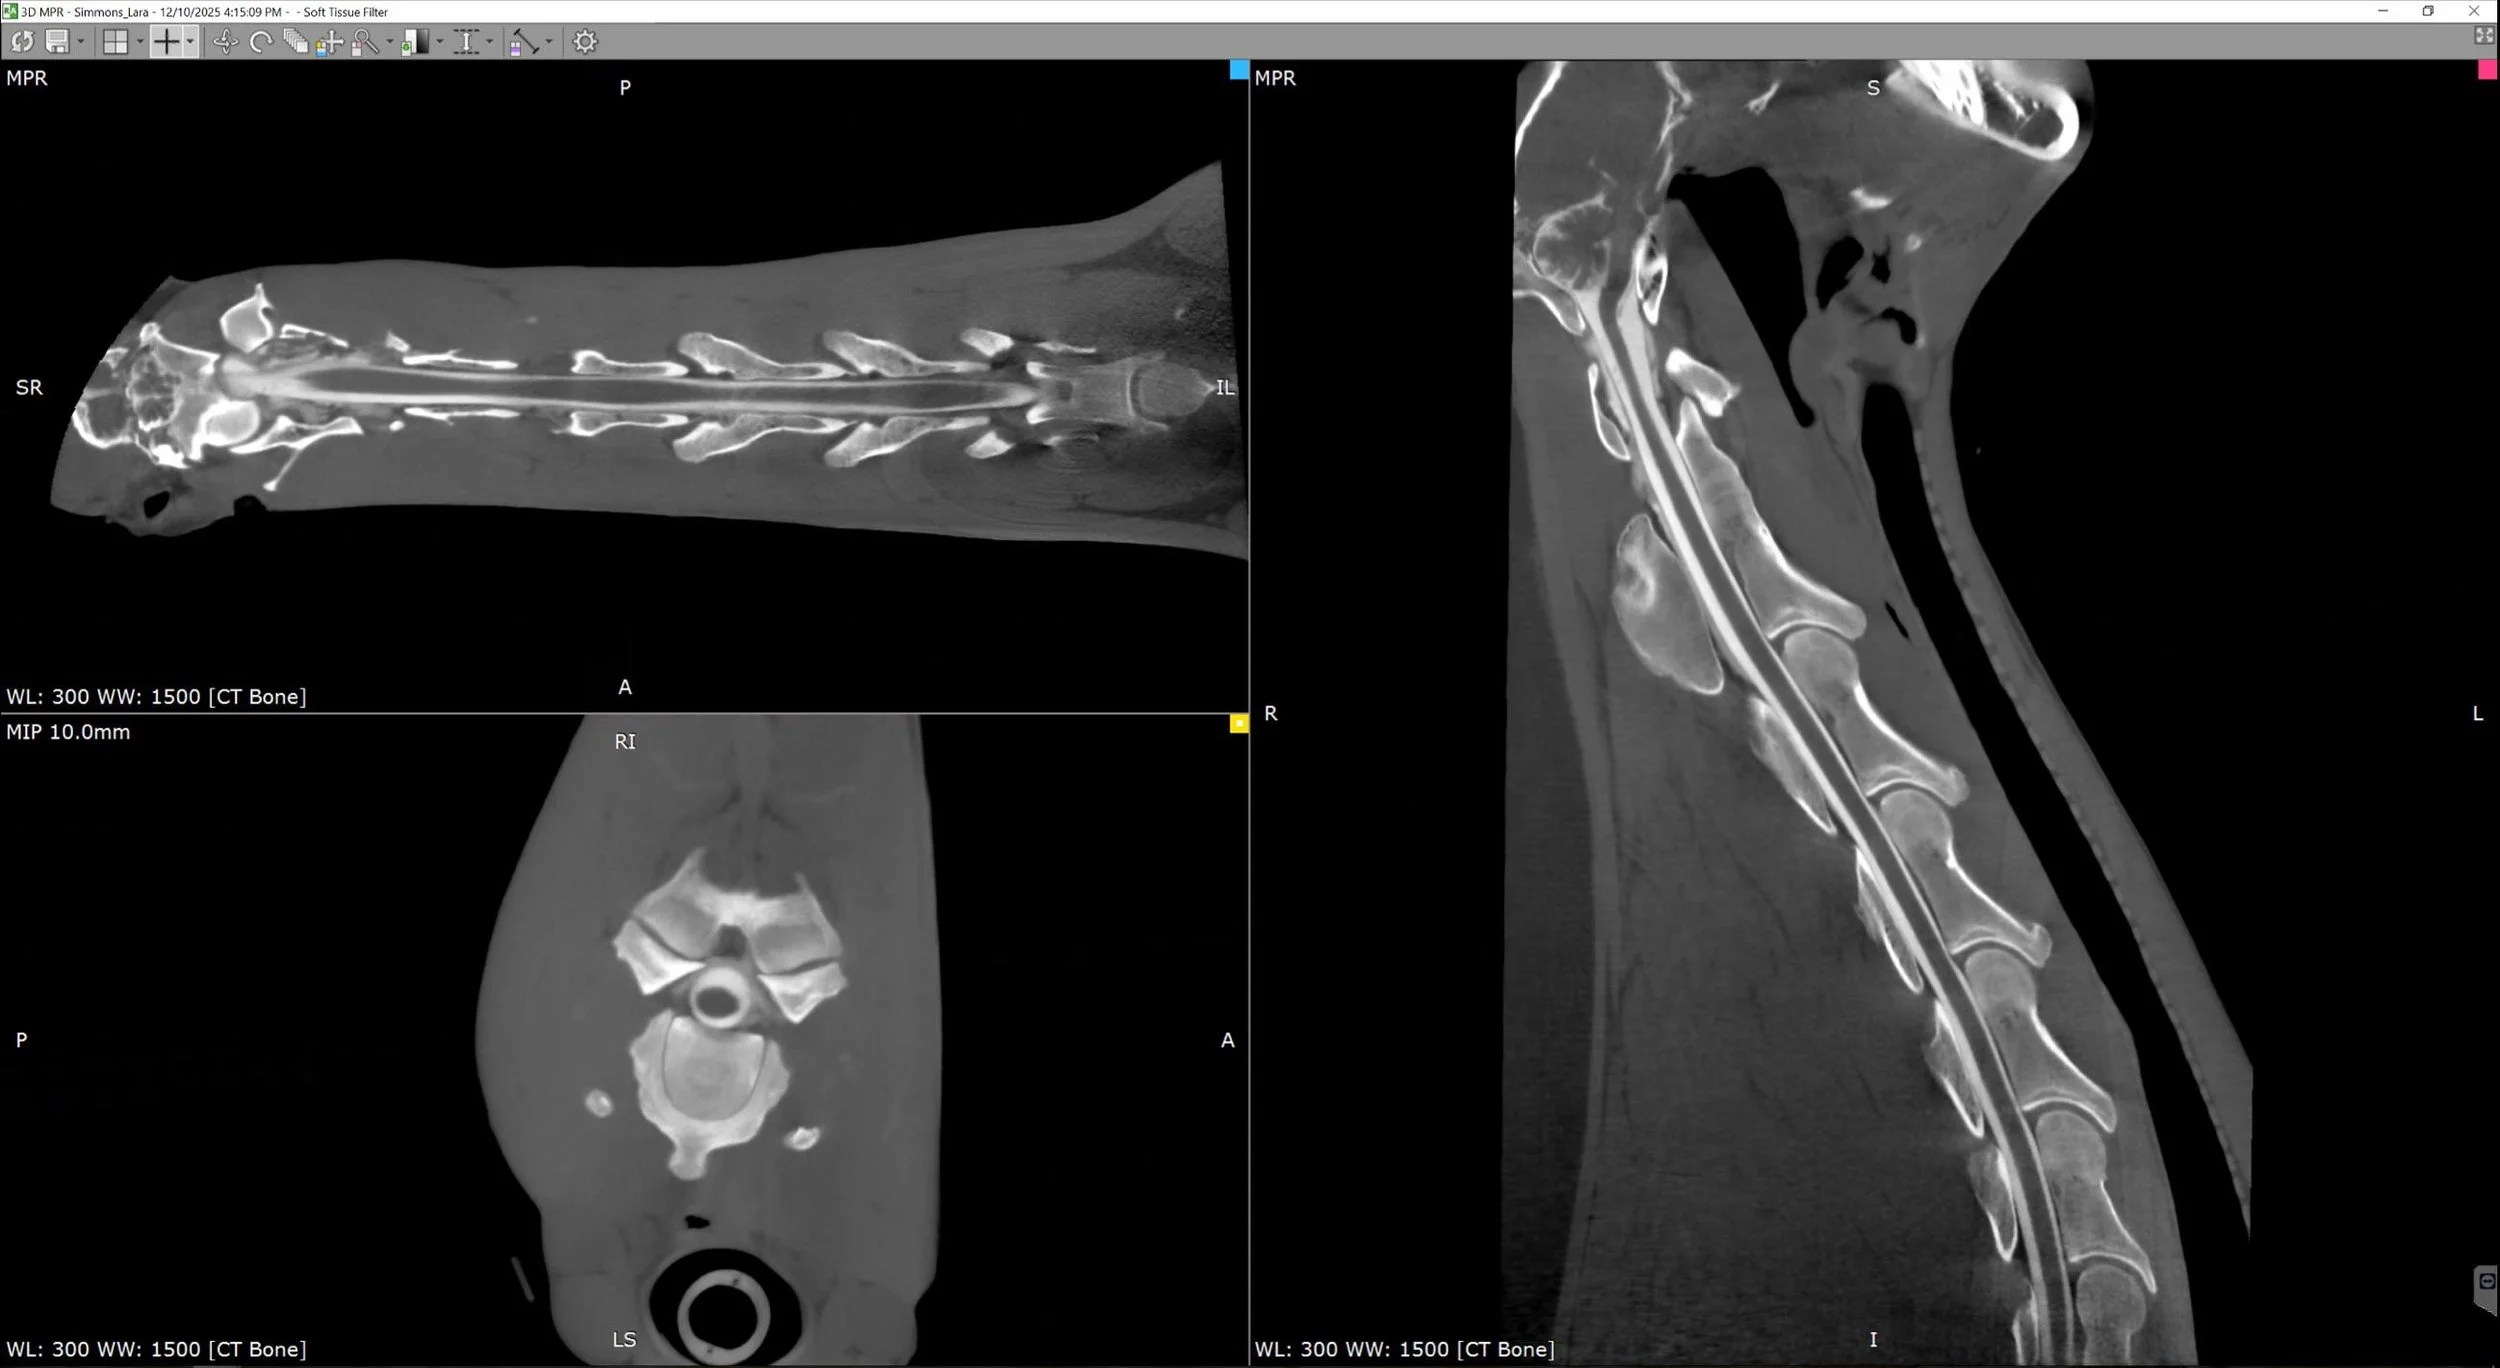

STANDING LIMB IMAGING